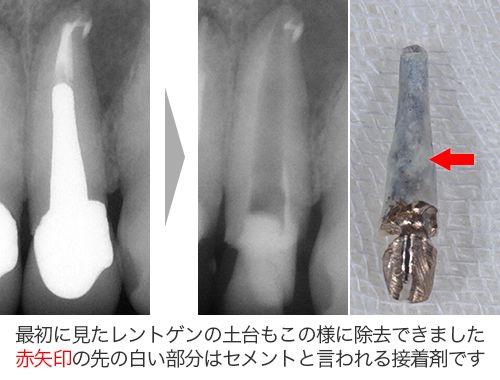

地味ーに少しずつ少しずつ金属の土台を削って、少しでも心配ならレントゲンを撮ってと手間暇惜しまずかけて除去したのです。

大阪の根管治療の専門の先生がこの方法を発明しまして、以下の写真の様にマイナスドライバーを2本使ってテコの原理を用い金属の土台を除去します。

80%以上この方法で金属の土台は除去することが可能です。

先ほども言いましたが、この方法はここ数年で根管治療の世界で脚光を浴びているのですが、実は私はもっと前から行っていました。

実は院長(宇毛先生)が10年以上も前からこの方法で金属の土台を除去していたのです。それを私は教わっていたからです。本当にこのテクニックは凄いです。院長も凄いと思います。

歯を全く削らず、しかも短時間で出来るのです。症例にもよりますが、だいたい数分でできます。以前の様に地味ーに削っていく方法だと20分以上かかったものです。